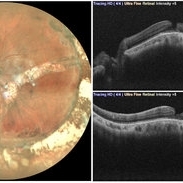

Macular Pseudo-Hole in a Buckled Eye

Fundus Photograph and Optical Coherence Tomography of left eye showing a macular pseudo-hole in a buckled eye.

Photographer: Dr. Akansha Sharma-Retina Foundation, Ahmedabad

Condition/keywords: macular hole, macular pseudohole, scleral buckle